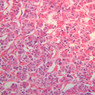

Examine slide B-56 (H&E [2.5x, 10x, 20x, 40x-labeled] [10x, 20x, 40x-labeled] [20x, 40x] [10x, 20x, 40x-labeled] [10x, 20x, 40x]). The connective tissue capsule of each parathyroid gland is continuous with that of the thyroid gland. It extends into the substance of the gland, dividing it into poorly defined lobules. Fat cells may separate the groups of cells and increase with age. Note the rich capillary network. The parenchyma is composed of two types of cells: (1) Principal or chief cells and (2) oxyphil cells. The polygonal chief cell is by far the more numerous cell type. Its nucleus is centrally located and has a vesicular chromatin pattern with a prominent nucleolus and its cytoplasm stains rather lightly. Oxyphil cells, which are less regular in shape and considerably larger than chief cells, are scattered singly or in small clusters. Their nuclei are smaller and more condensed than those of the chief cells and, owing to a very rich complement of mitochondria, their cytoplasm is distinctly acidophilic.